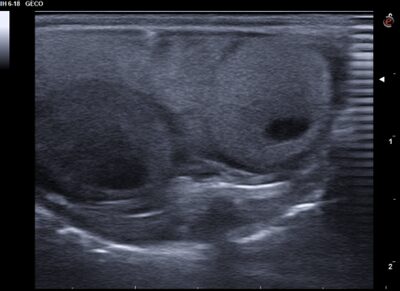

Seguiment: Porten el saure als 15 dies de la primera visita, segueix inflat i cada vegada menja menys, no han vist en el terrari la posada. Es realitza ecografia de control i s’observen 4 fol·licles preovulatoris, 2 d’ells hiperecogènics i 2 amb aspecte normal, i la típica imatge ecogènica amb centre circular hipoecogènic (figura 4).

Fig 4. Presència de fol·licles hiperecogènics (asteriscs) i fol·licles preovulatoris normals, normoecogènics i amb el cercle anecogènic al seu interior. Imatge d’ecografia de la segona visita.